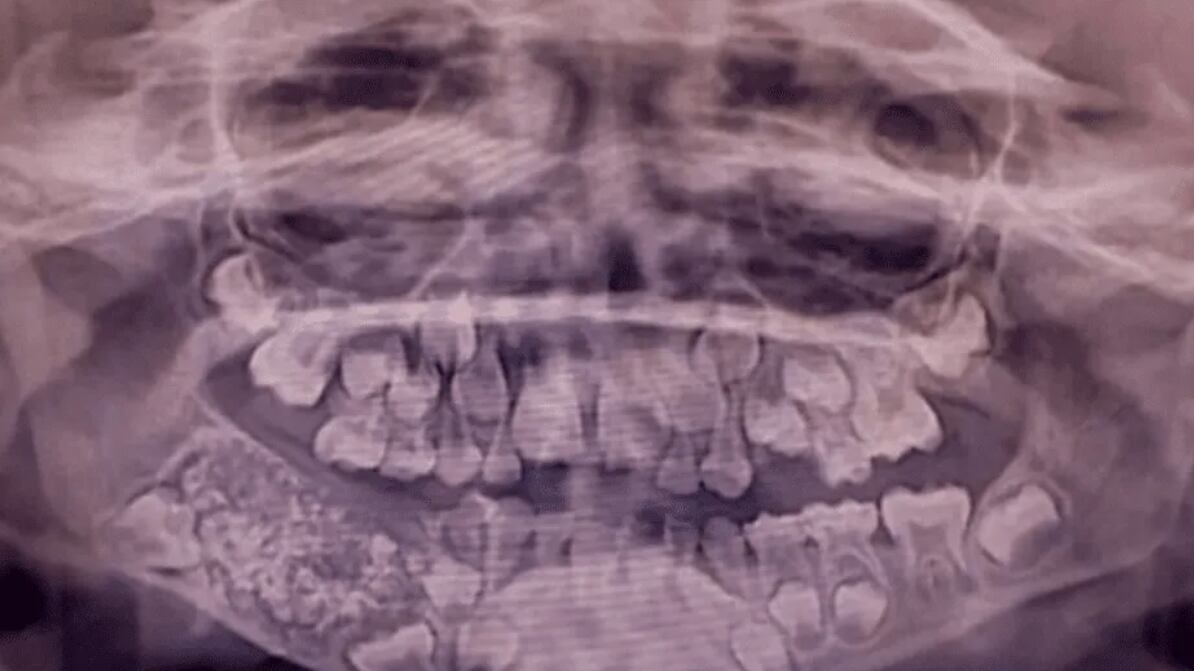

El menor presentaba una hinchazón progresiva en la parte inferior derecha de la mandíbula desde los tres años, pero la falta de cooperación impidió una evaluación inicial efectiva. Al reaparecer los síntomas a los siete años, los especialistas realizaron radiografías y una tomografía que revelaron una “masa en forma de bolsa” con múltiples estructuras duras en su interior.

Durante la intervención, el equipo médico removió esa masa, la cual pesaba aproximadamente 200 gramos. Al abrirla, se encontraron 526 piezas dentales diminutas —entre 0,1 mm y 15 mm— cada una con corona, raíz y capa de esmalte, lo que los médicos compararon con “perlas en una ostra”.